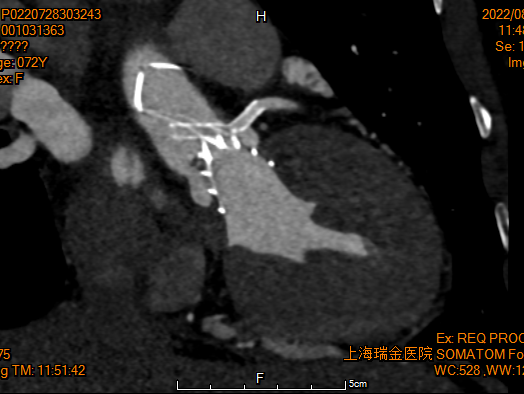

术后1w——冠脉CTA

检查结果-即刻超声

动脉瓣瓣周轻度反流。

经主动脉口收缩期血流最大速度约1.5m/s,最大跨瓣压差约10mmHg。

术后24h心超

● EF 68% 。

● 主动脉瓣未见明显反流。经主动脉瓣口收缩期最大流速约1.9m/s,最大压差约15mmHg,心率约95bpm。

● 二尖瓣轻度反流 。

● 三尖瓣轻度反流,最大反流速度约2.9m/s,估测肺动脉收缩压约44mmHg。

● 经左室流出道收缩期最大流速约1.9 m/s。